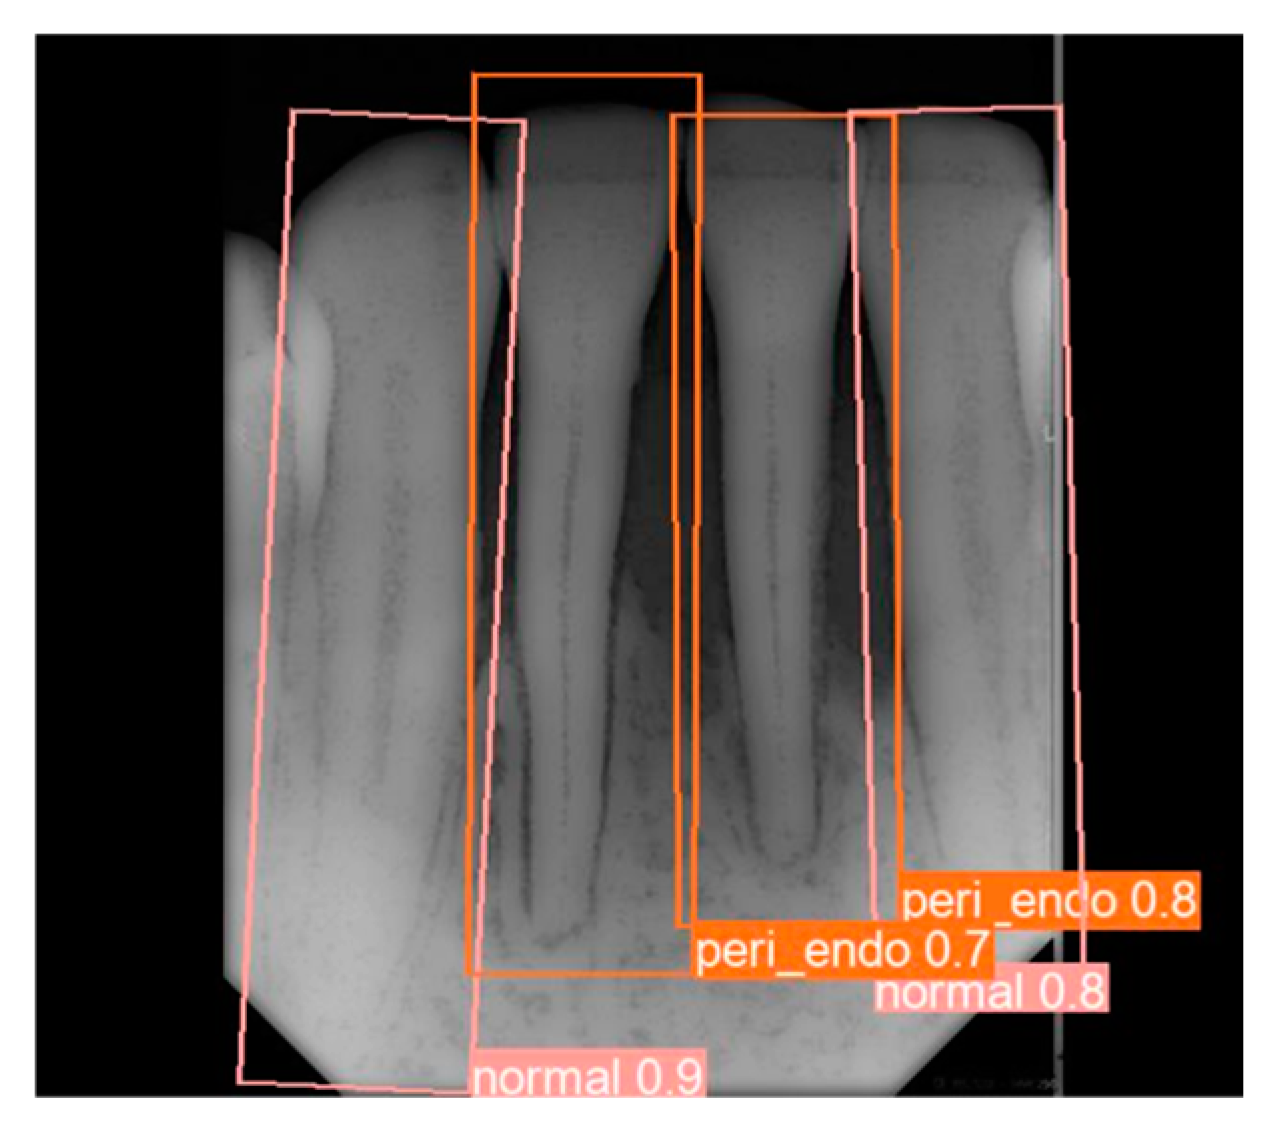

3.1. YOLO Detection and Image Segmentation